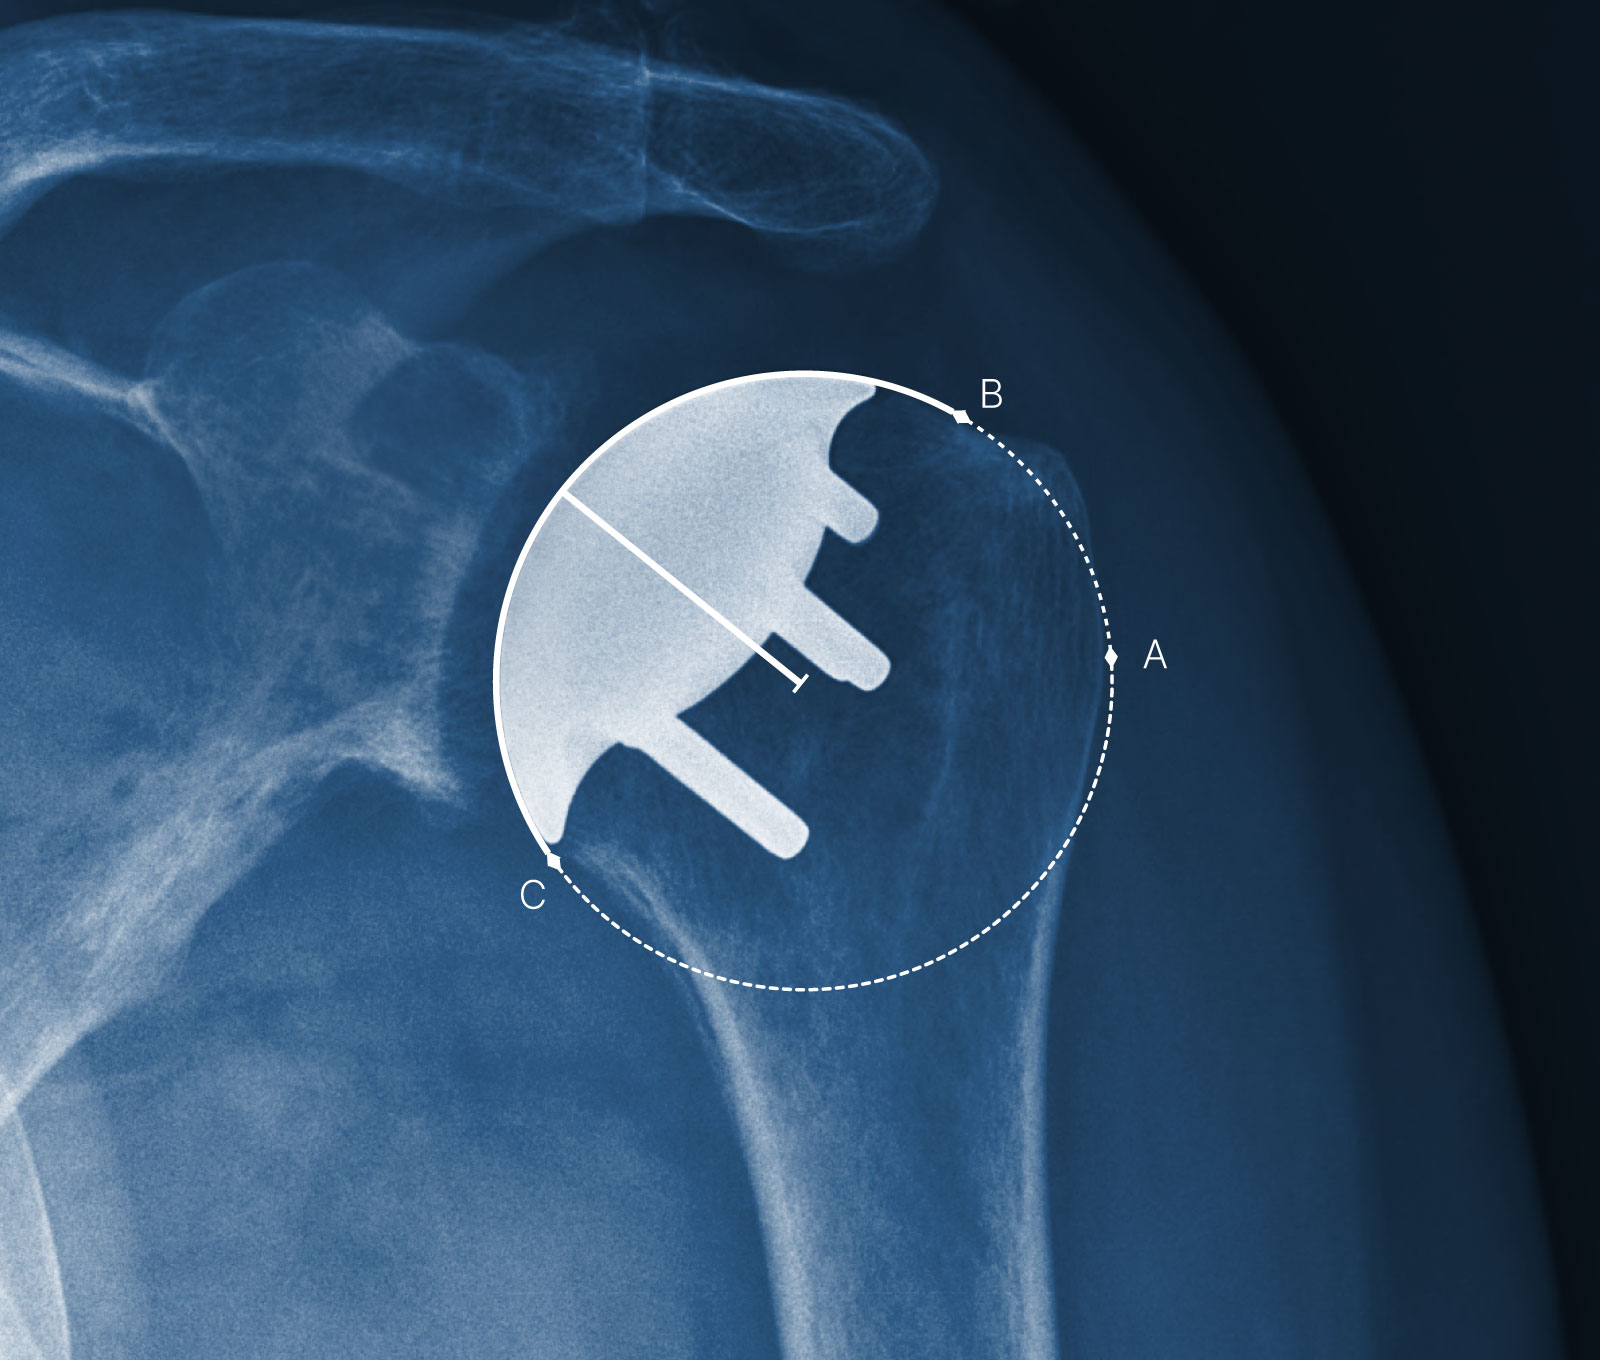

Shoulder replacement procedures performed with Catalyst shoulder systems have numerous benefits compared to other systems, including a more natural-feeling shoulder after surgery, 1-3 the potential for faster recovery, 1 greater preservation of strong, healthy bone, 4 and more.